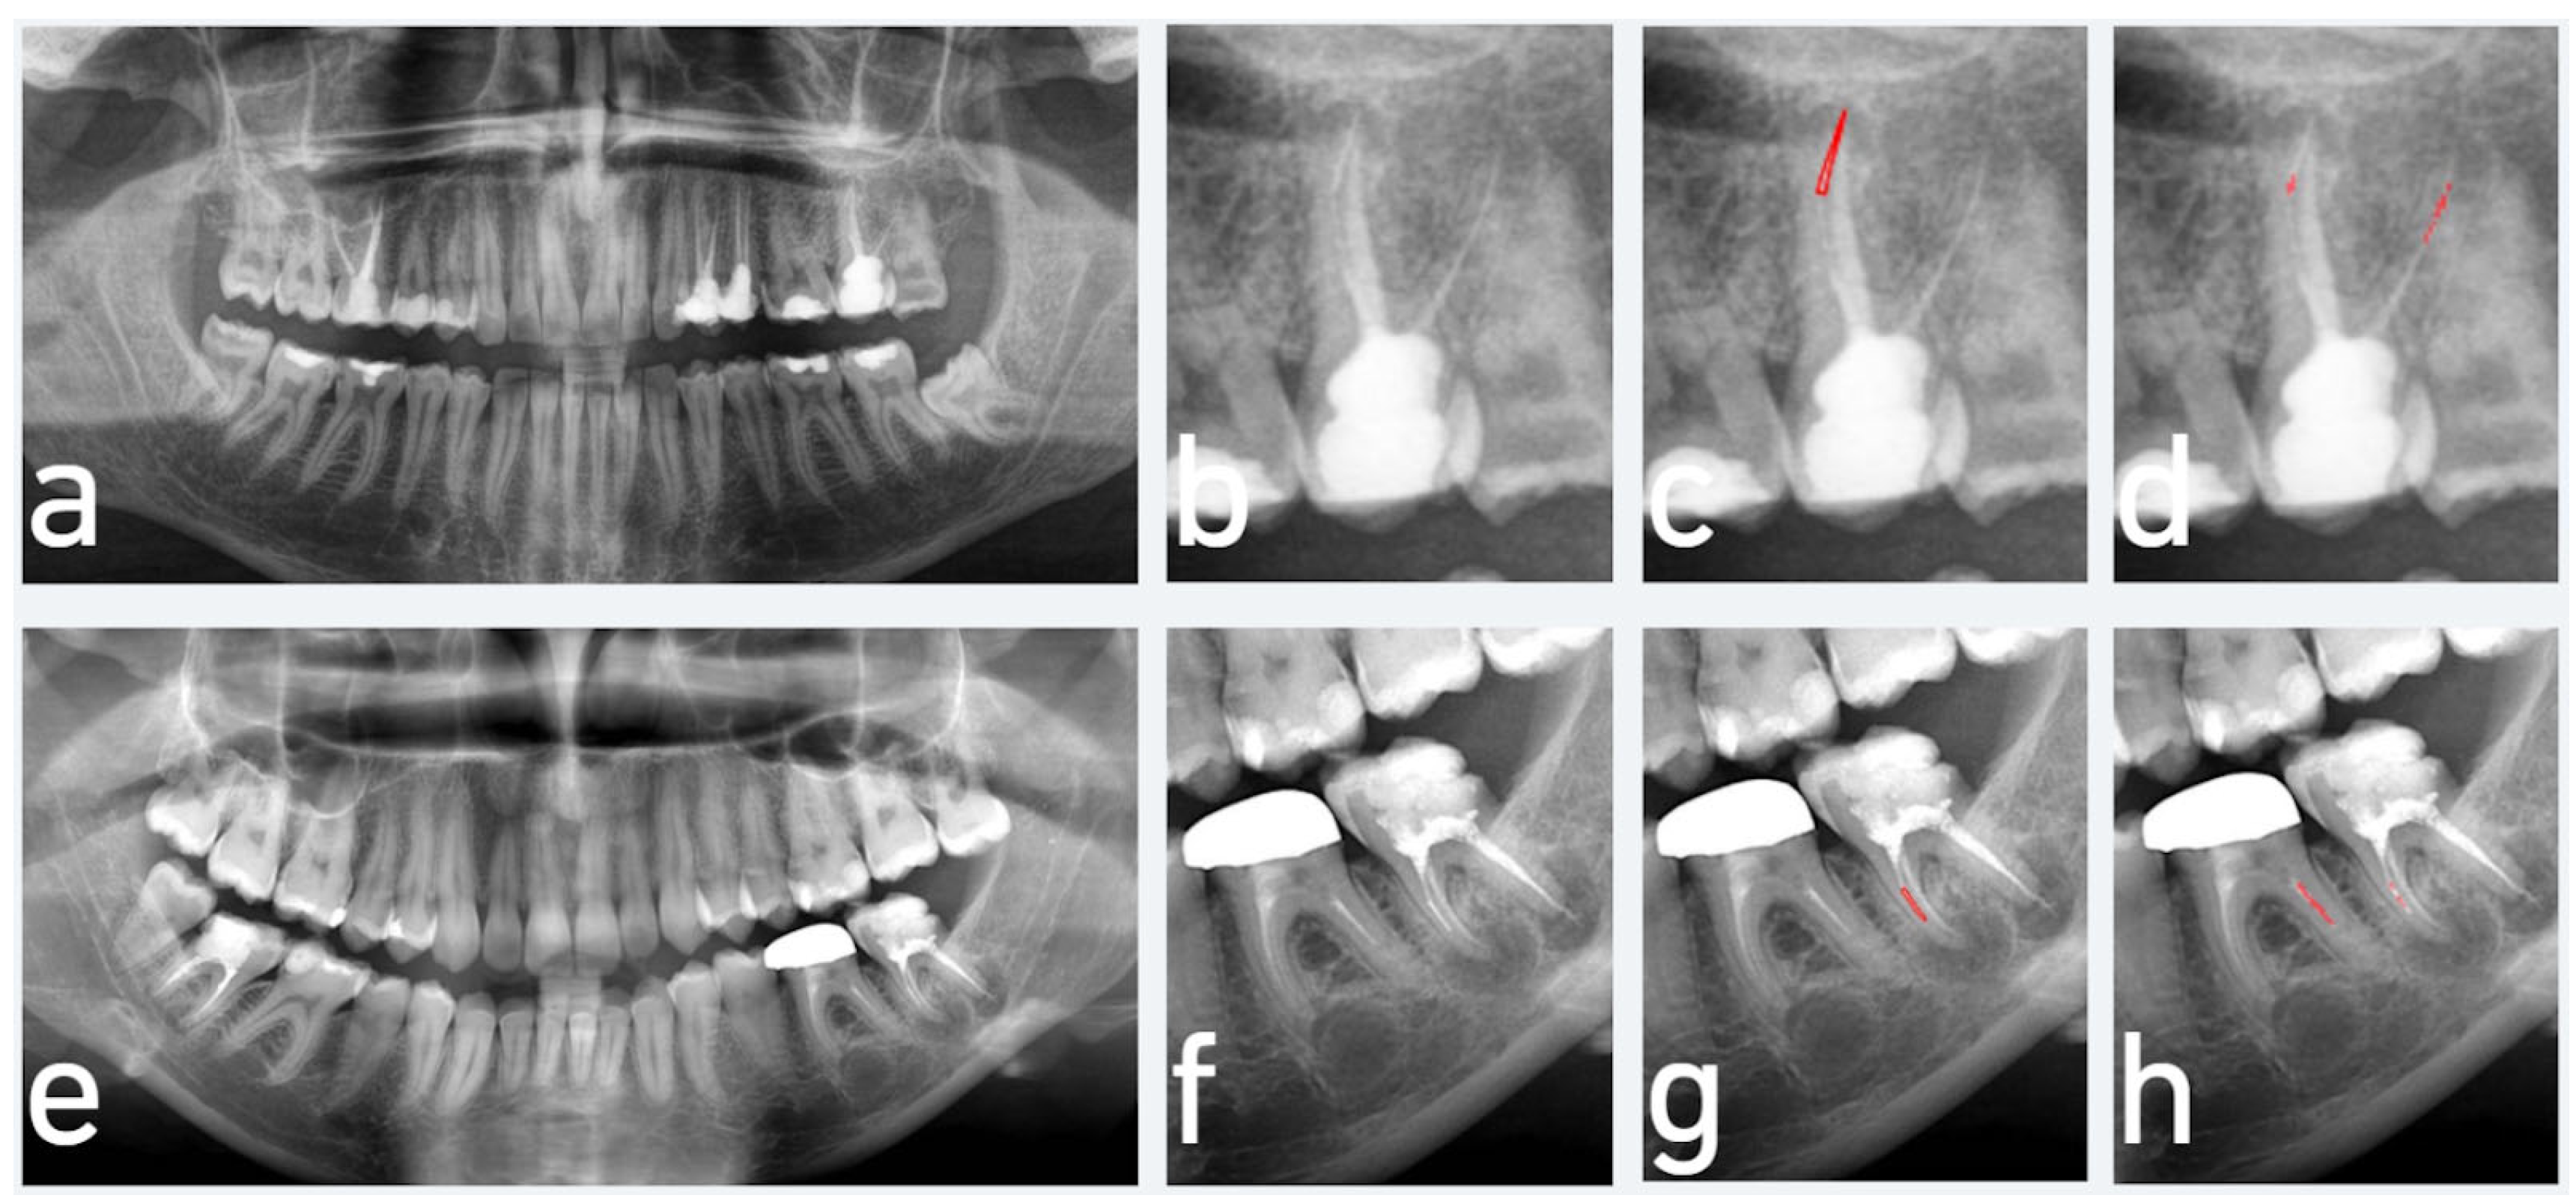

2.1. Data Preparation and Labelling